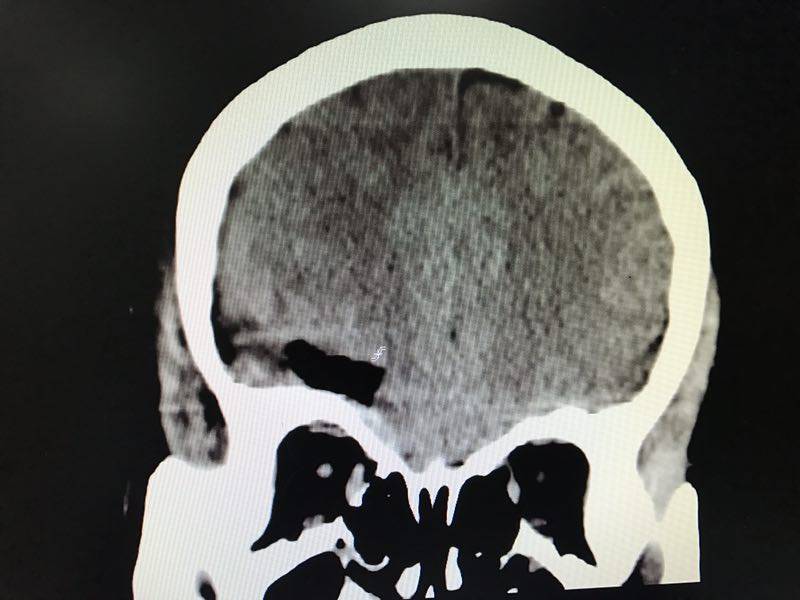

當(dāng)時(shí),它住在一位52歲阿姨的腦子里,本來(lái)和平共處,相安無(wú)事。有一天不小心喝多了吃撐了,一下子胖了不少,將正常的腦組織擠了一下,阿姨頓時(shí)就抗議了,暈得天旋地轉(zhuǎn),嘔吐不止,還觸發(fā)了她的冠心病,出現(xiàn)了胸悶、心悸的癥狀。正當(dāng)腦膜瘤為自己的“蝴蝶效應(yīng)”洋洋得意時(shí),阿姨被送到了惠州市第三人民醫(yī)院神經(jīng)外科,一個(gè)頭顱CT便初步將它鎖定。

術(shù)前三維血管重建

以上為術(shù)前腦膜瘤不同切面pose照(冠狀位、矢狀位、軸位)